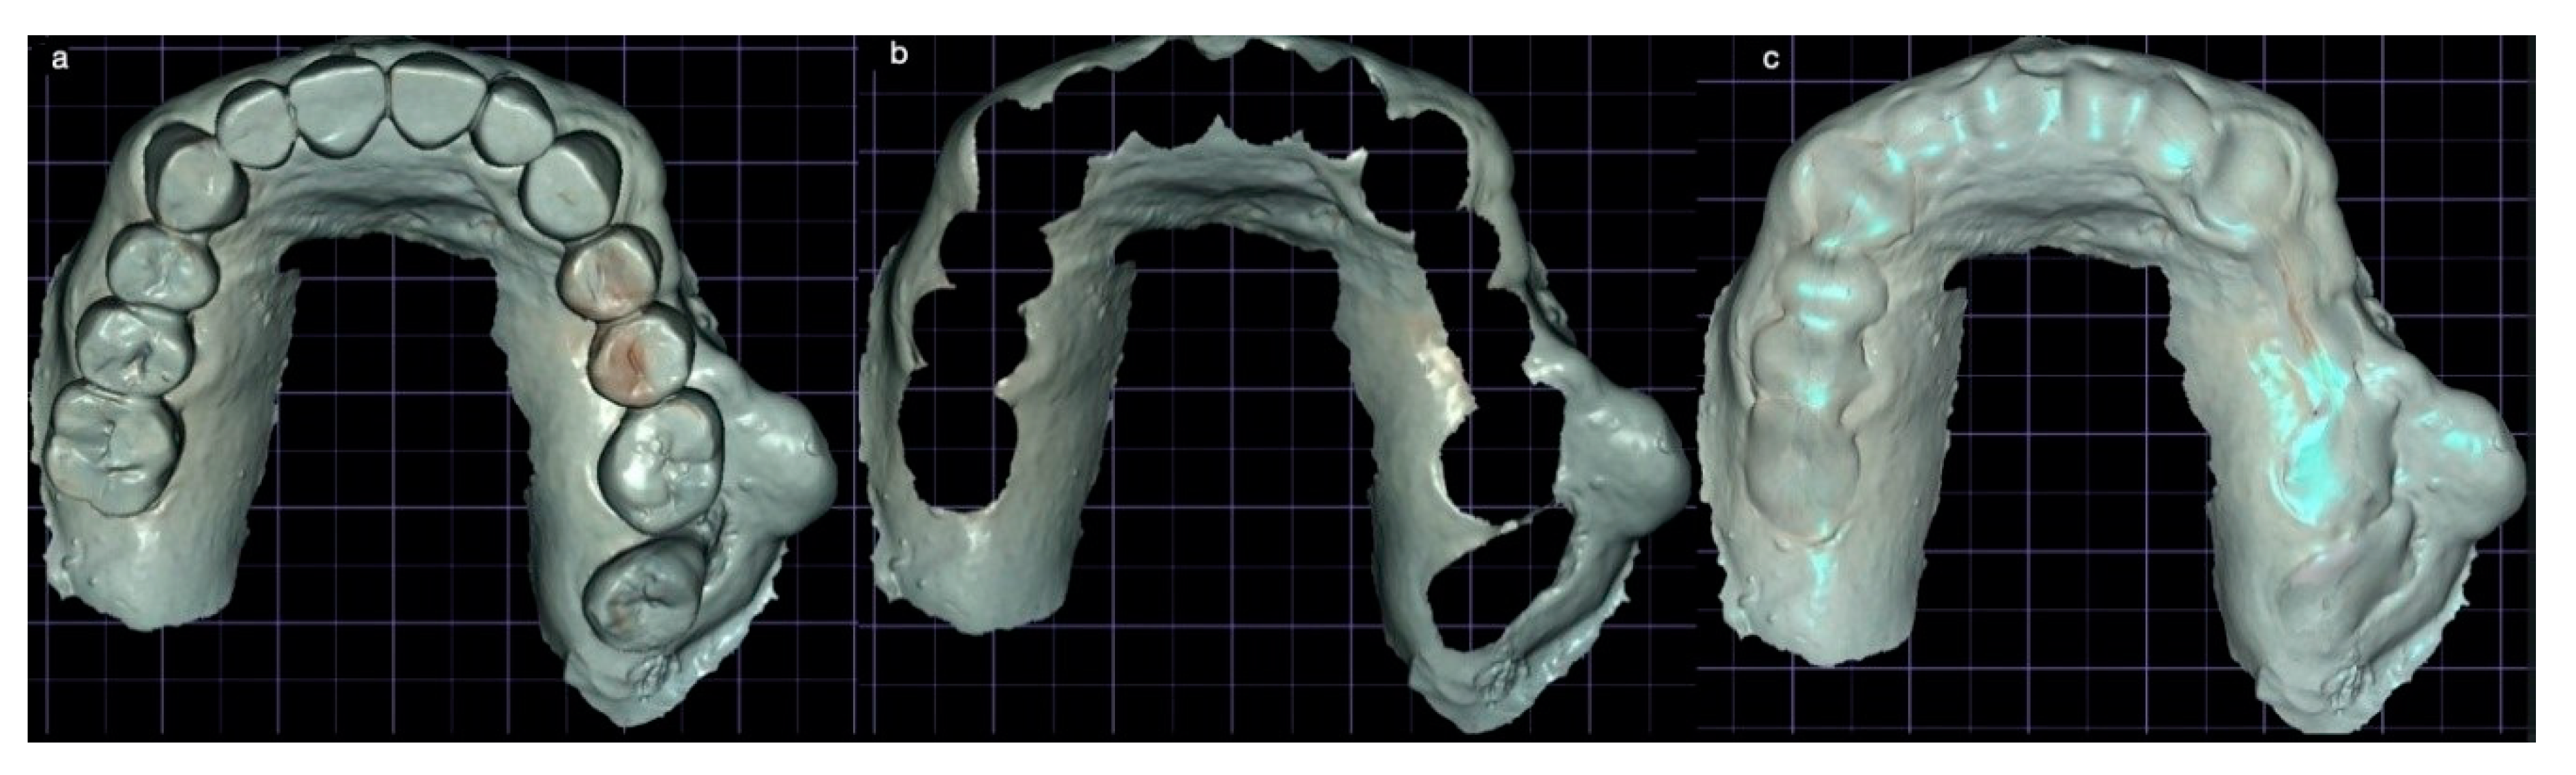

3.1. SCAI Approach Clinical Case